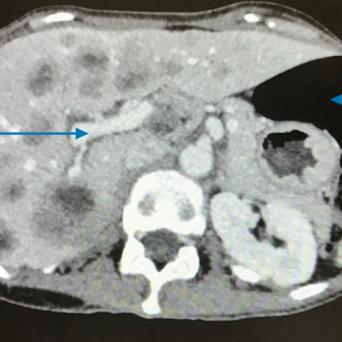

L’image

du jour

Illustration.